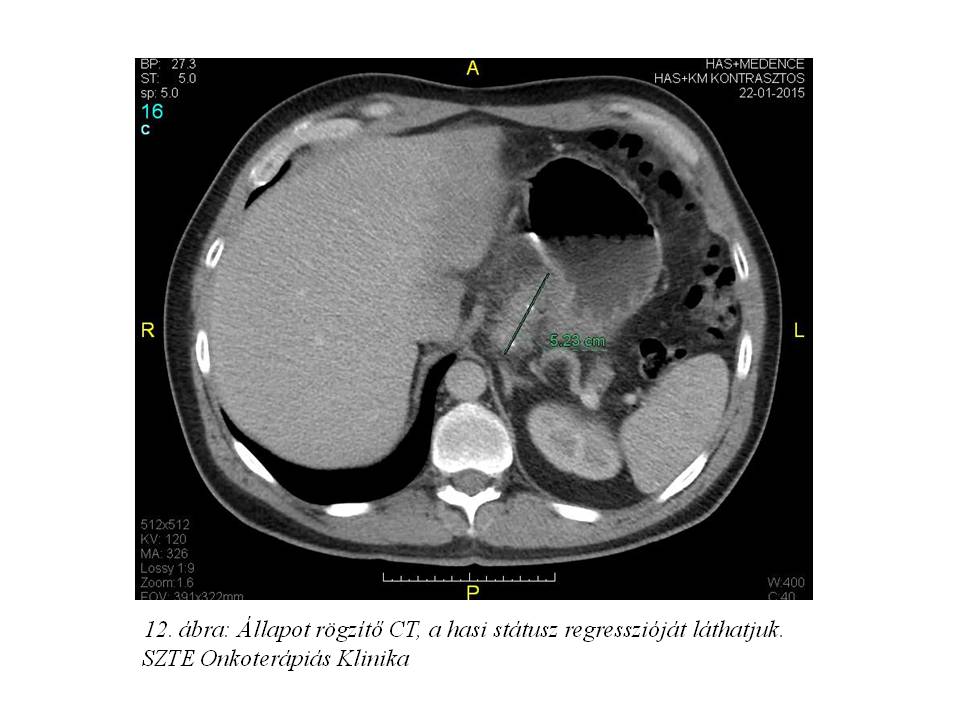

A re-staging vizsgálatként elvégzett mellkas, has-kismedence CT (2015.01.22. 12. ábra) kisfokú regressziót írt le, az operábilitás elbírálása érdekében sebészeti konzíliumot kértünk. 2015.05.07-én az Uzsoki Utcai Kórház onkosebészeti osztályán total gastrectomia történt D2 lymphadenectomiával. A műtét utáni felépülés teljes, bőrtünetei a komplex ellátást követően mérséklődtek. Onkoteam döntés alapján a beteg rutin követése javasolt.